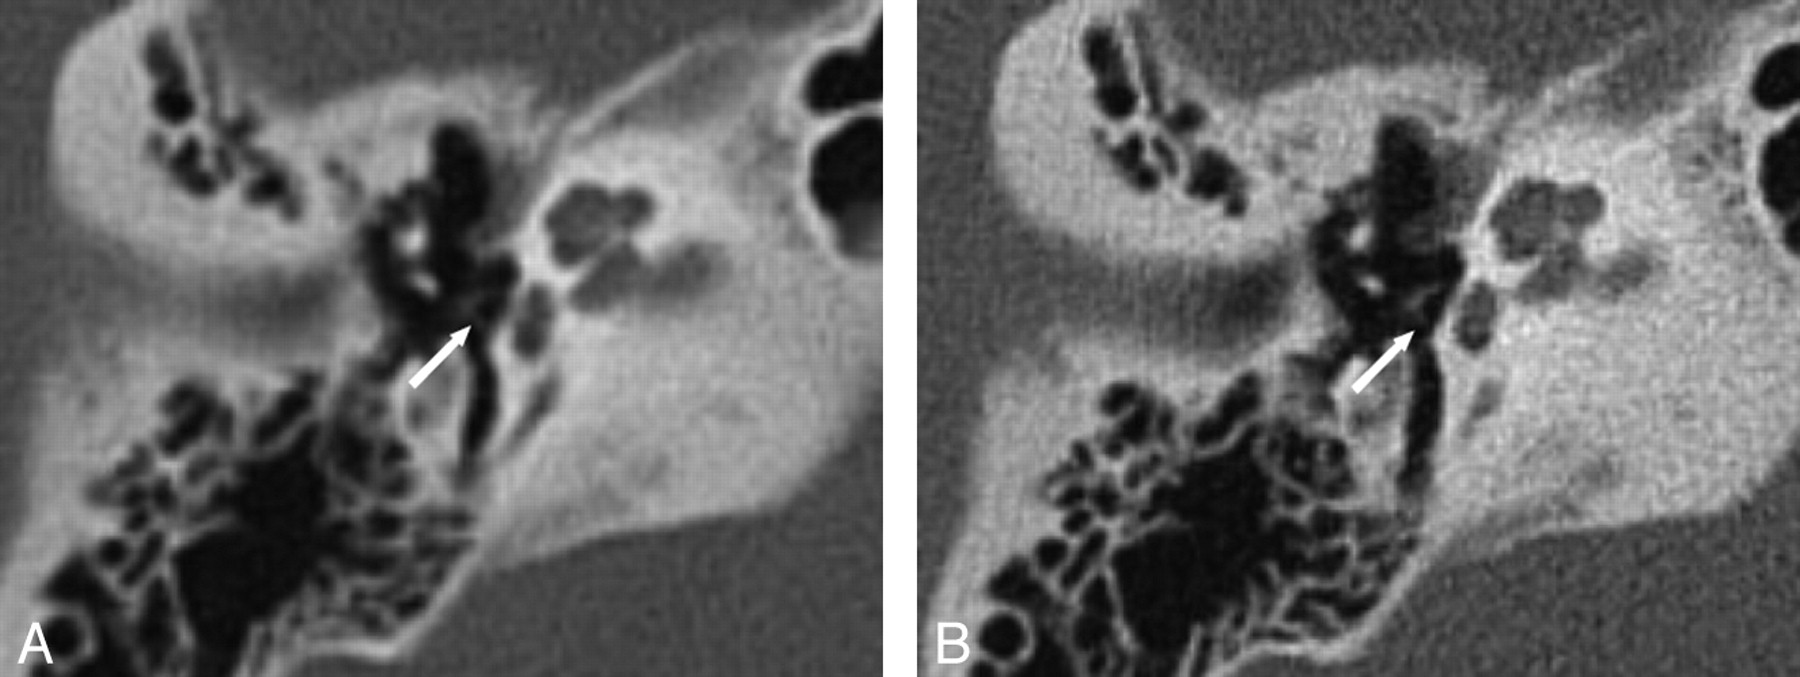

After the Bonferroni correction, a significant difference was found between SST and MSCT for the lateral mallear ligament (Fig 4) and the bony septum between the upper and middle turn of the cochlea (Fig 5). The former was seen more clearly with MSCT, whereas the latter was seen better with SST.

Temporal bone coronal MPR, section thickness 0.8 mm. The lateral mallear ligament can hardly be seen with SST (A), whereas it is clearly shown with MSCT (B).

Temporal bone axial MPR, section thickness 0.8 mm. The bony septum between the apical and middle turn of the cochlea (arrows) can be seen more clearly with SST (A) than with MSCT (B), where it can hardly be found.

The bony septum between the apical and middle turn of the cochlea could be judged significantly better with SST. The integrity of the latter together with, for example, the entire cochlear morphology is of special importance in the preoperative assessment of the inner ear before cochlear implantation8⇓–10 or for the diagnosis of labyrinthitis ossificans.11 Using SST could be an advantage in these patients.

The second anatomic structure that showed a significant difference between SST and MSCT was the lateral mallear ligament, which was imaged more clearly with MSCT. Because either fixation or detachment of the mallear ligaments may lead to impaired transduction of acoustic stimuli, a proper visualization of these delicate anatomic structures is necessary12 and can be achieved with high-resolution CT.13 Therefore, on the basis of our data, we recommend imaging of the mallear ligaments with MSCT rather than SST.